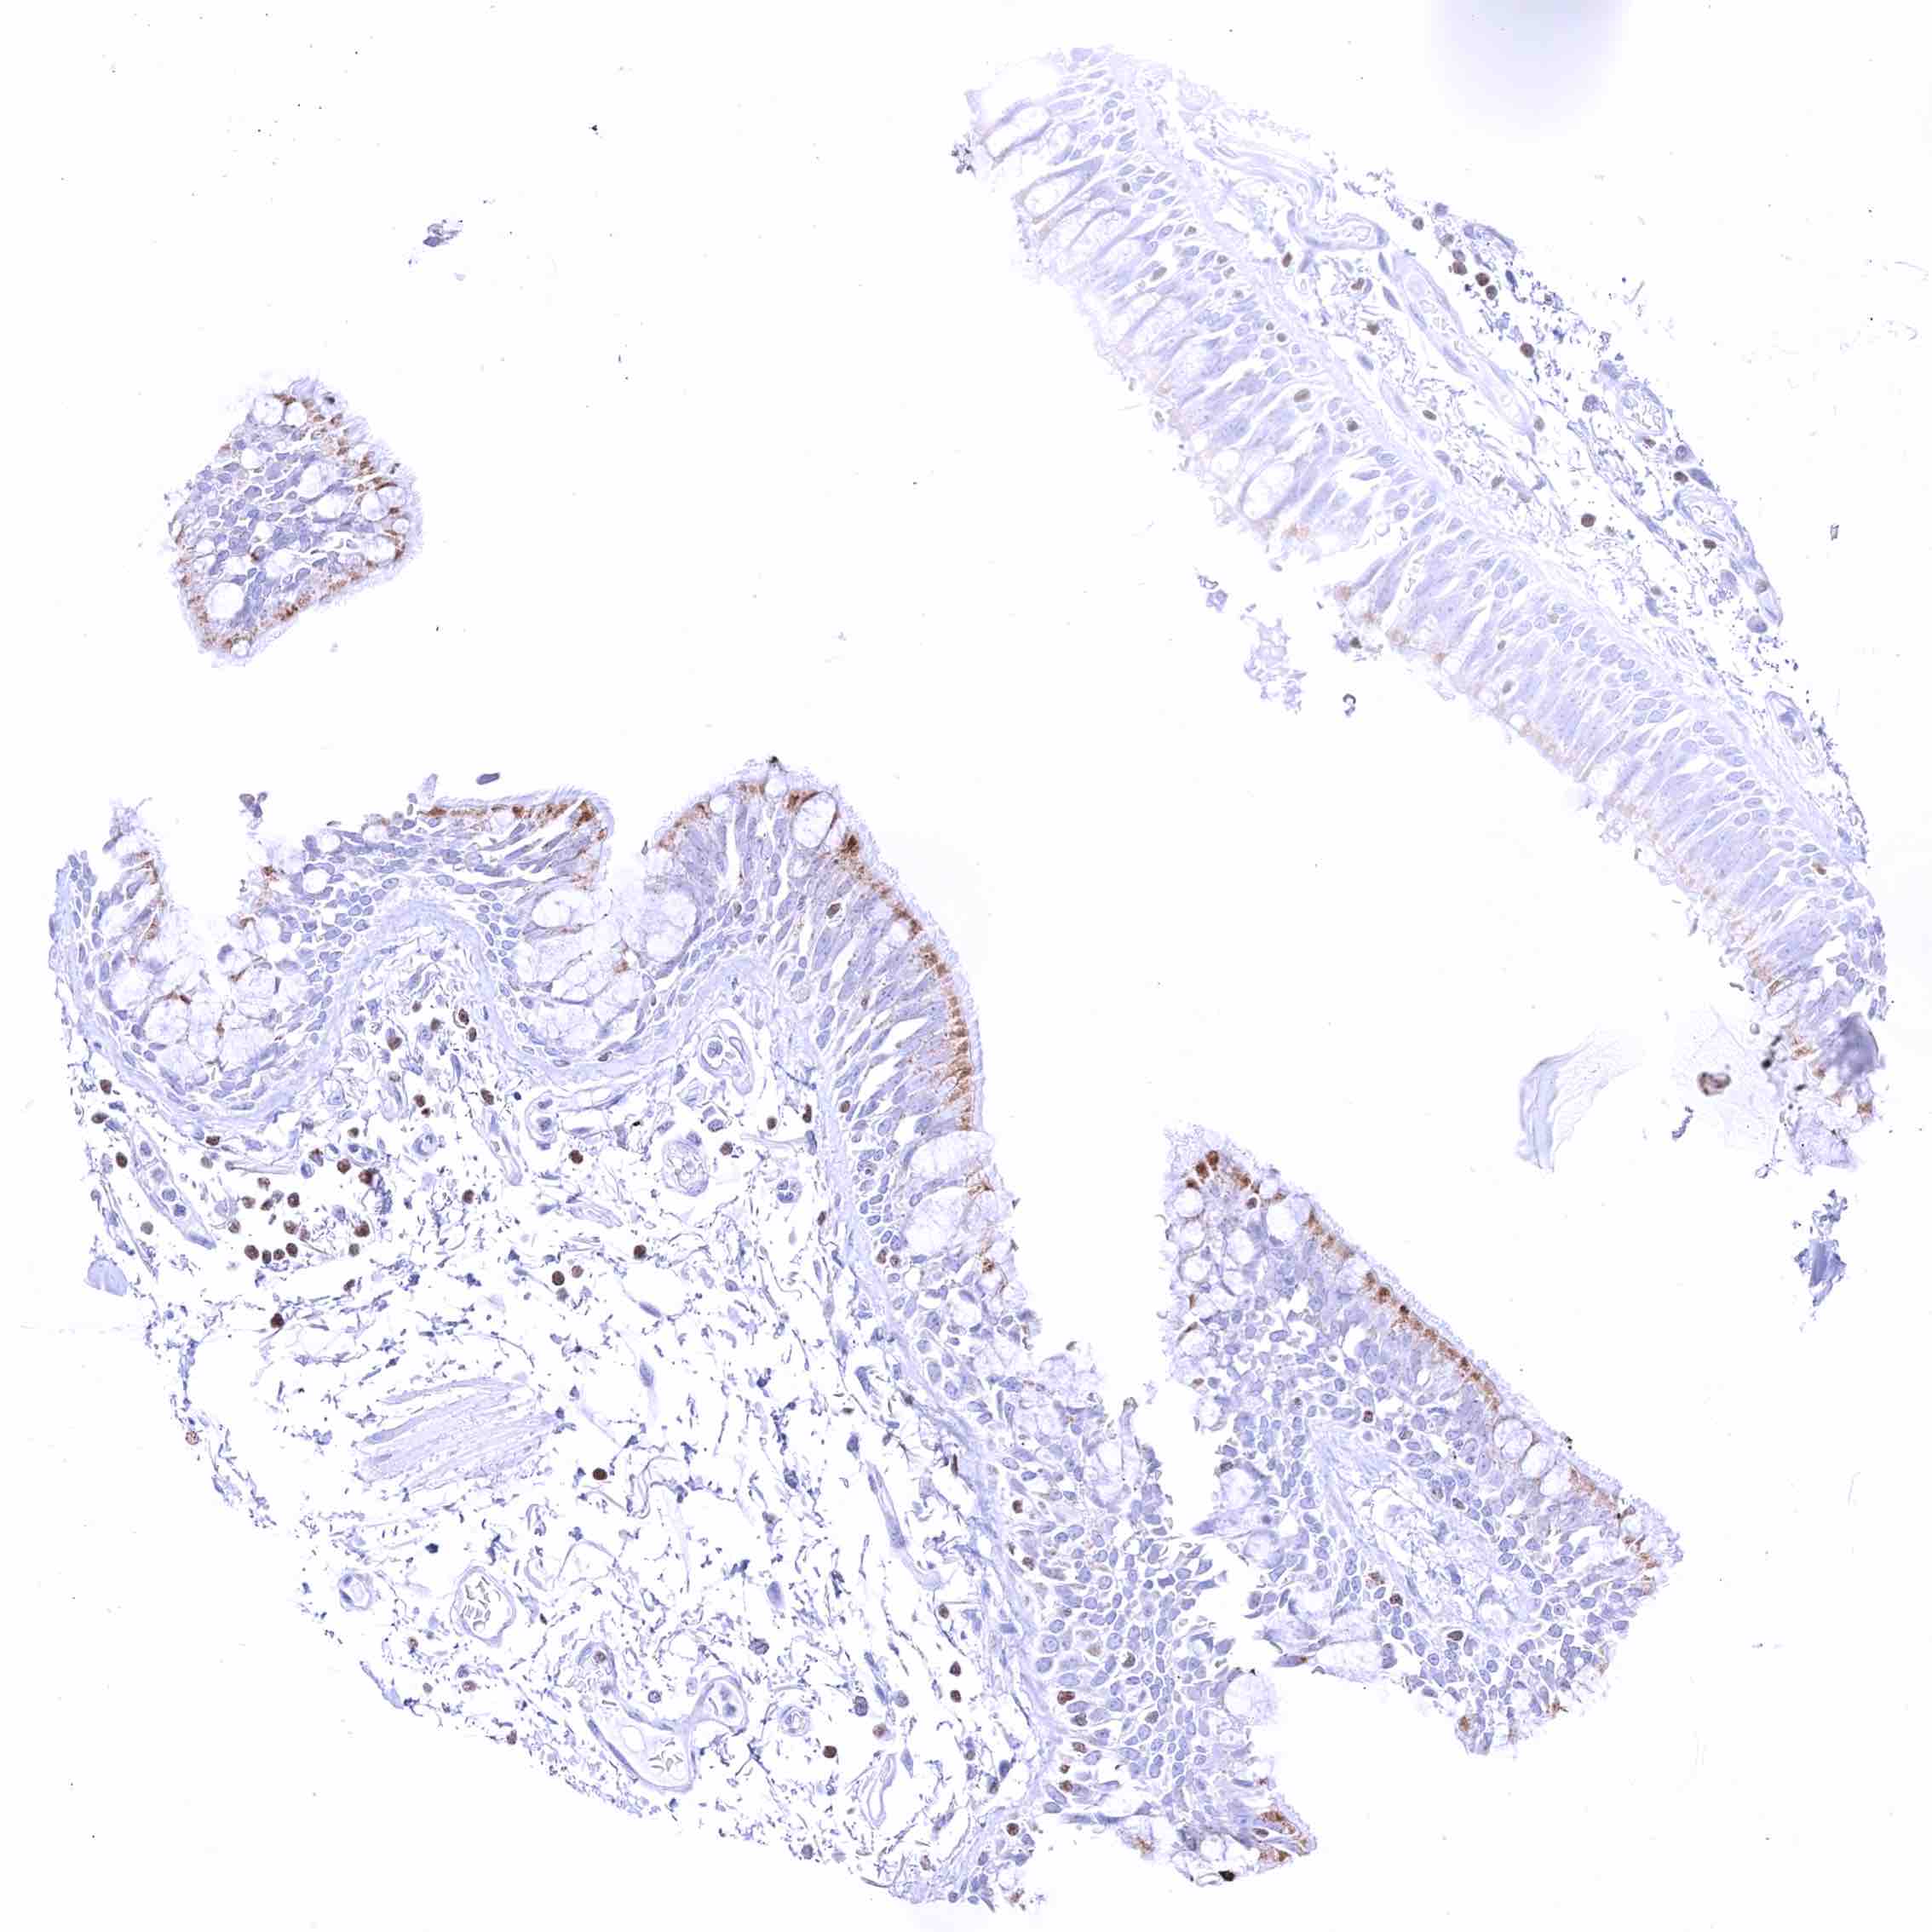

Rectum, mucosa – Nuclear GATA3 positivity of many lymphocytes.

Rectum, mucosa – Nuclear GATA3 positivity of some lymphocytes. Granular cytoplasmic GATA3 staining of epithelial cells.